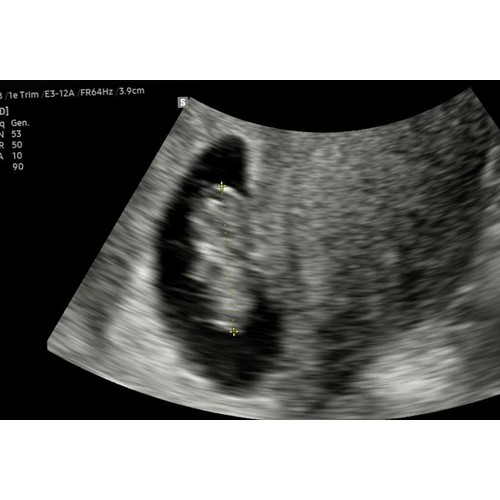

Ligt een beetje aan de verloskundige waar je zit. Bij de verloskundige waar ik bij zit is dit een medische echo. De vitaliteits echo. Waar ze kijken of er een gezonde zwangerschap is en of het een een of een meerling is. Dit doen ze vaak tussen de 7 en 9 weken.

Helaas moeilijk tezien gisteren echo gehad ban 8+5 maar mijn baarmoeder ligt nog wat verder naar achter dus niet zn hele helderen echo maar hartje klopt en alles was goed 😍😍